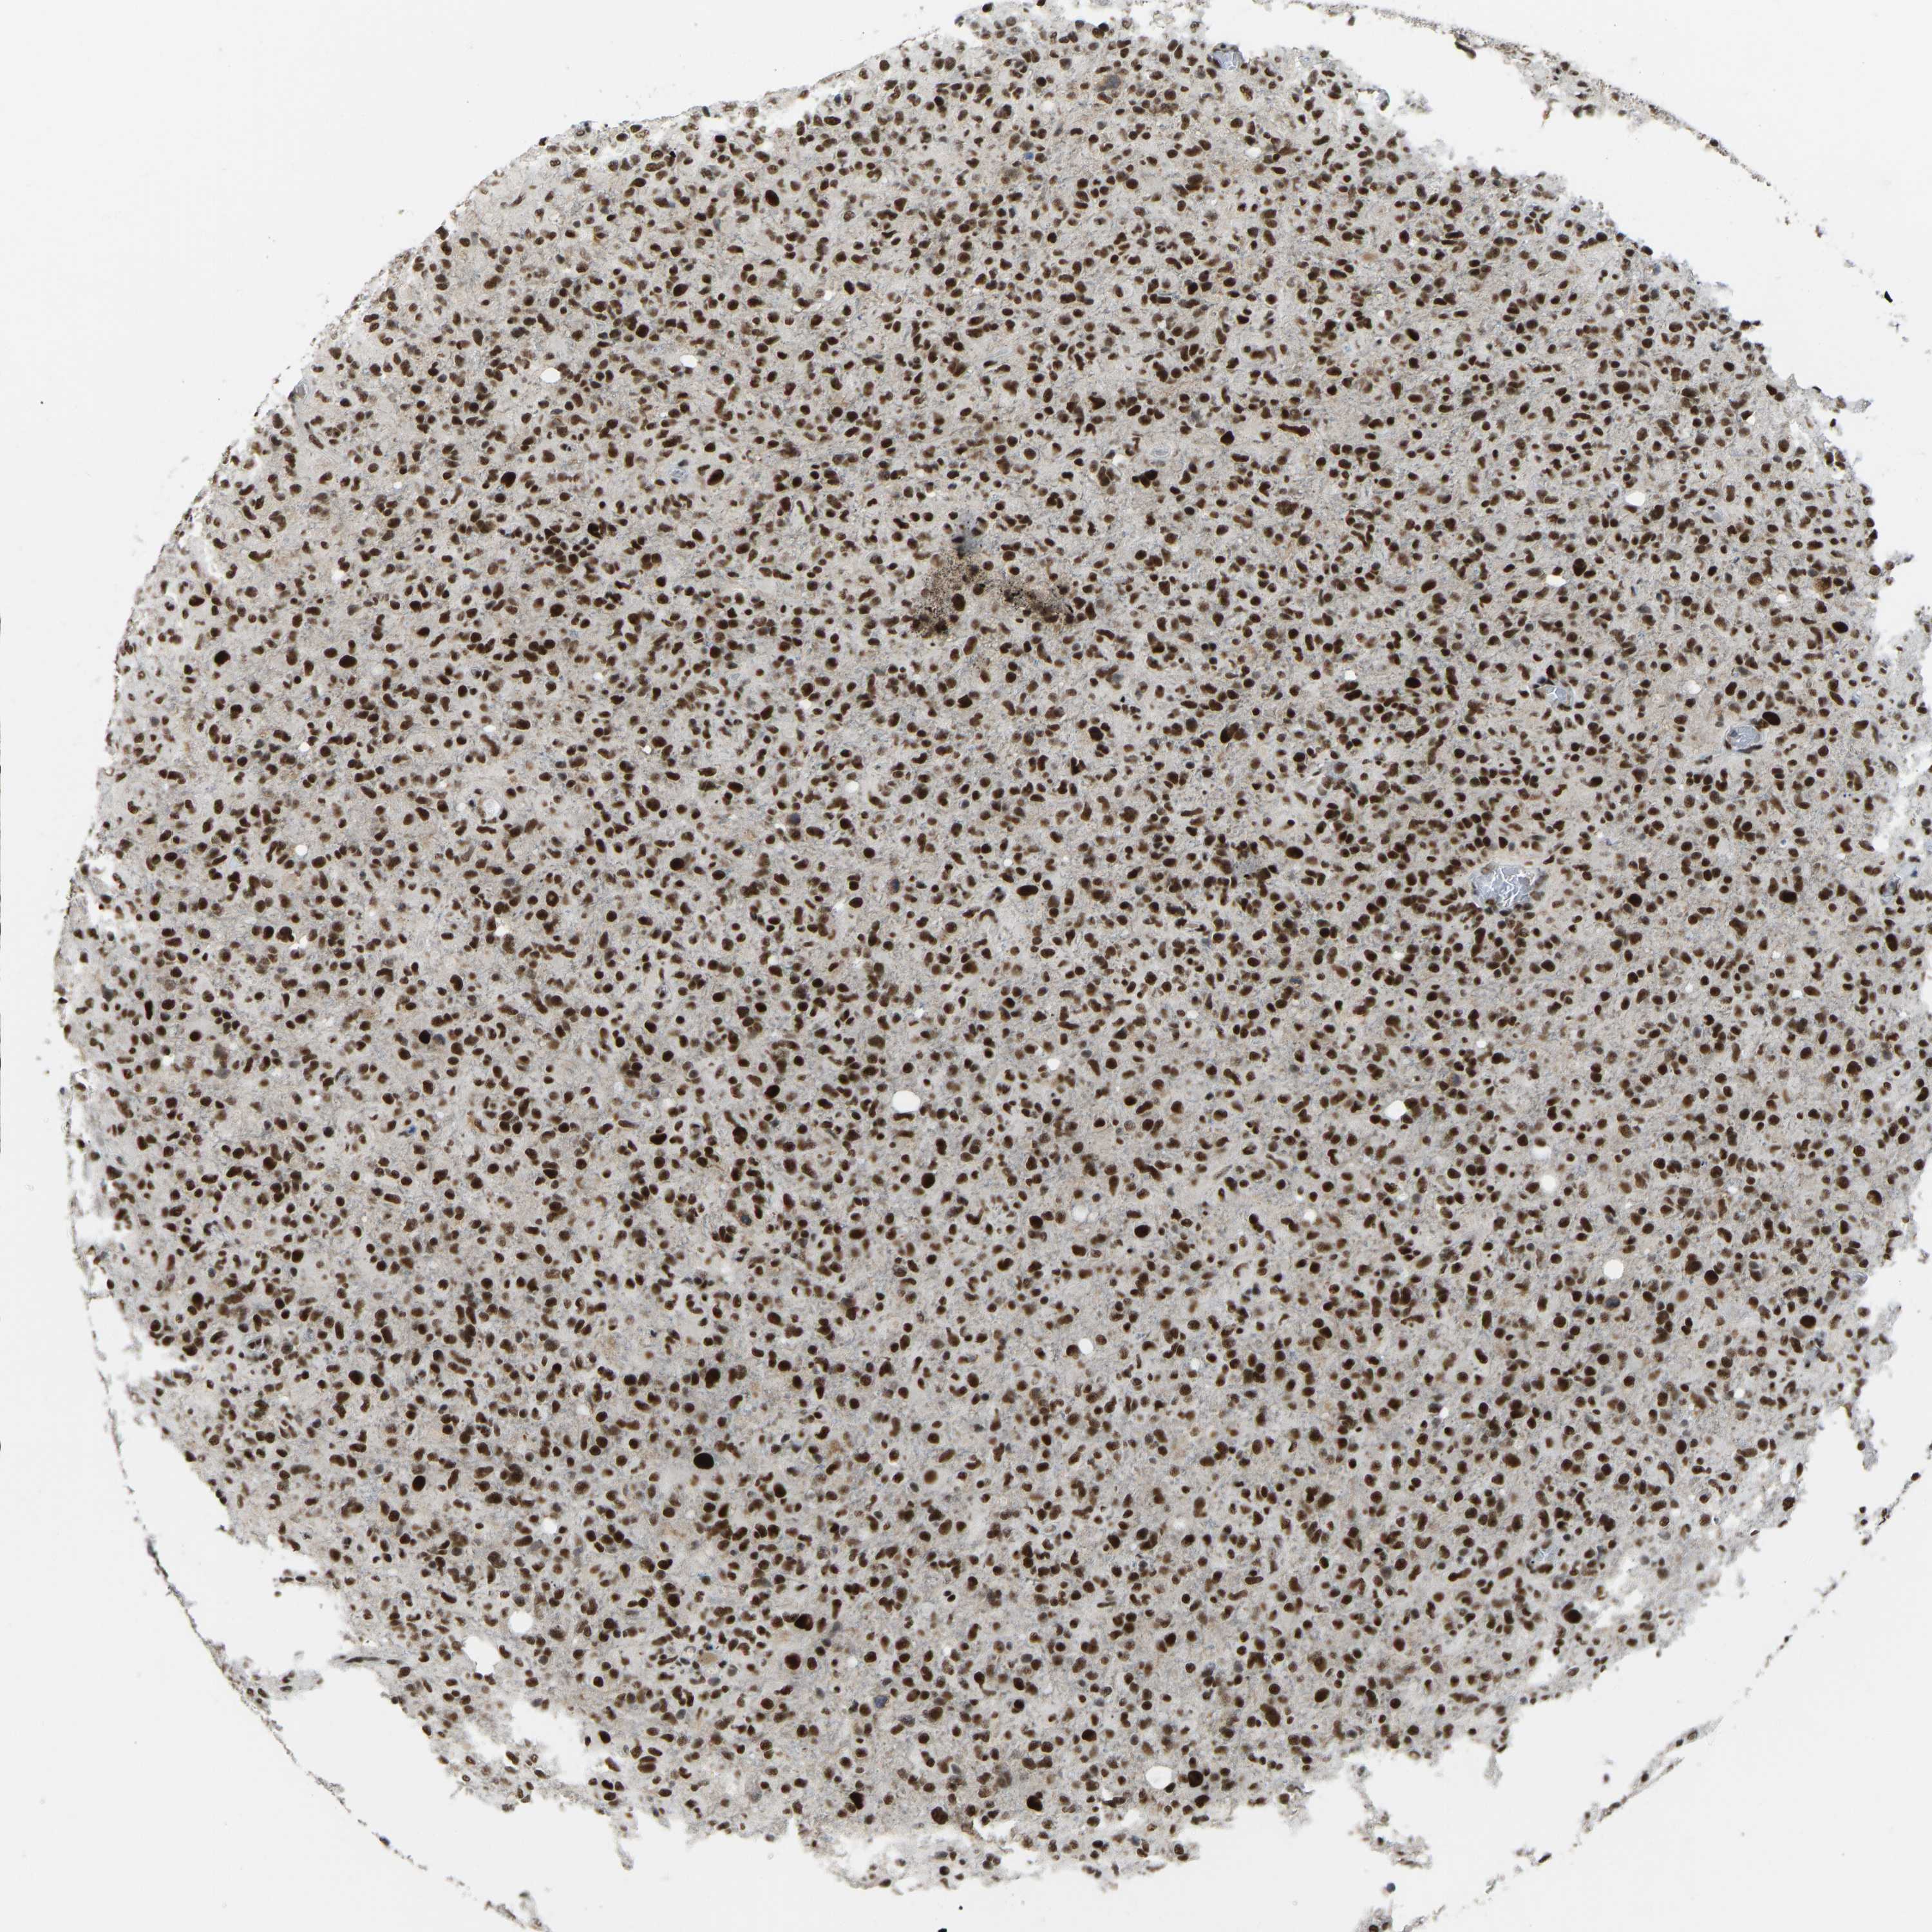

GLIOMA - Protein expressioni

A mouse-over function shows sample information and annotation data. Click on an image to view it in a full screen mode. Samples can be filtered based on level of antibody staining by selecting one or several of the following categories: high, medium, low and not detected. The assay and annotation is described here.

Note that samples used for immunohistochemistry by the Human Protein Atlas do not correspond to samples in the TCGA dataset.

Antibody stainingi

Antibody staining in the annotated cell types in the current human tissue is reported as not detected, low, medium, or high, based on conventional immunohistochemistry profiling in selected tissues. This score is based on the combination of the staining intensity and fraction of stained cells.

Each image is clickable and will lead to virtual microscopy that enables deeper exploration of all samples and also displays staining intensity scores, fraction scores and subcellular localization as well as patient and tissue information for each sample.

Antibody HPA017998

Antibody HPA018864

Staining

High

Medium

Low

Not detected

Intensity

Strong

Moderate

Weak

Negative

Quantity

>75%

75%-25%

<25%

None

Location

Nuclear

Cytoplasmic/membranous

Cytoplasmic/membranous,nuclear

Glioma, malignant, High grade

Glioma, malignant, Low grade